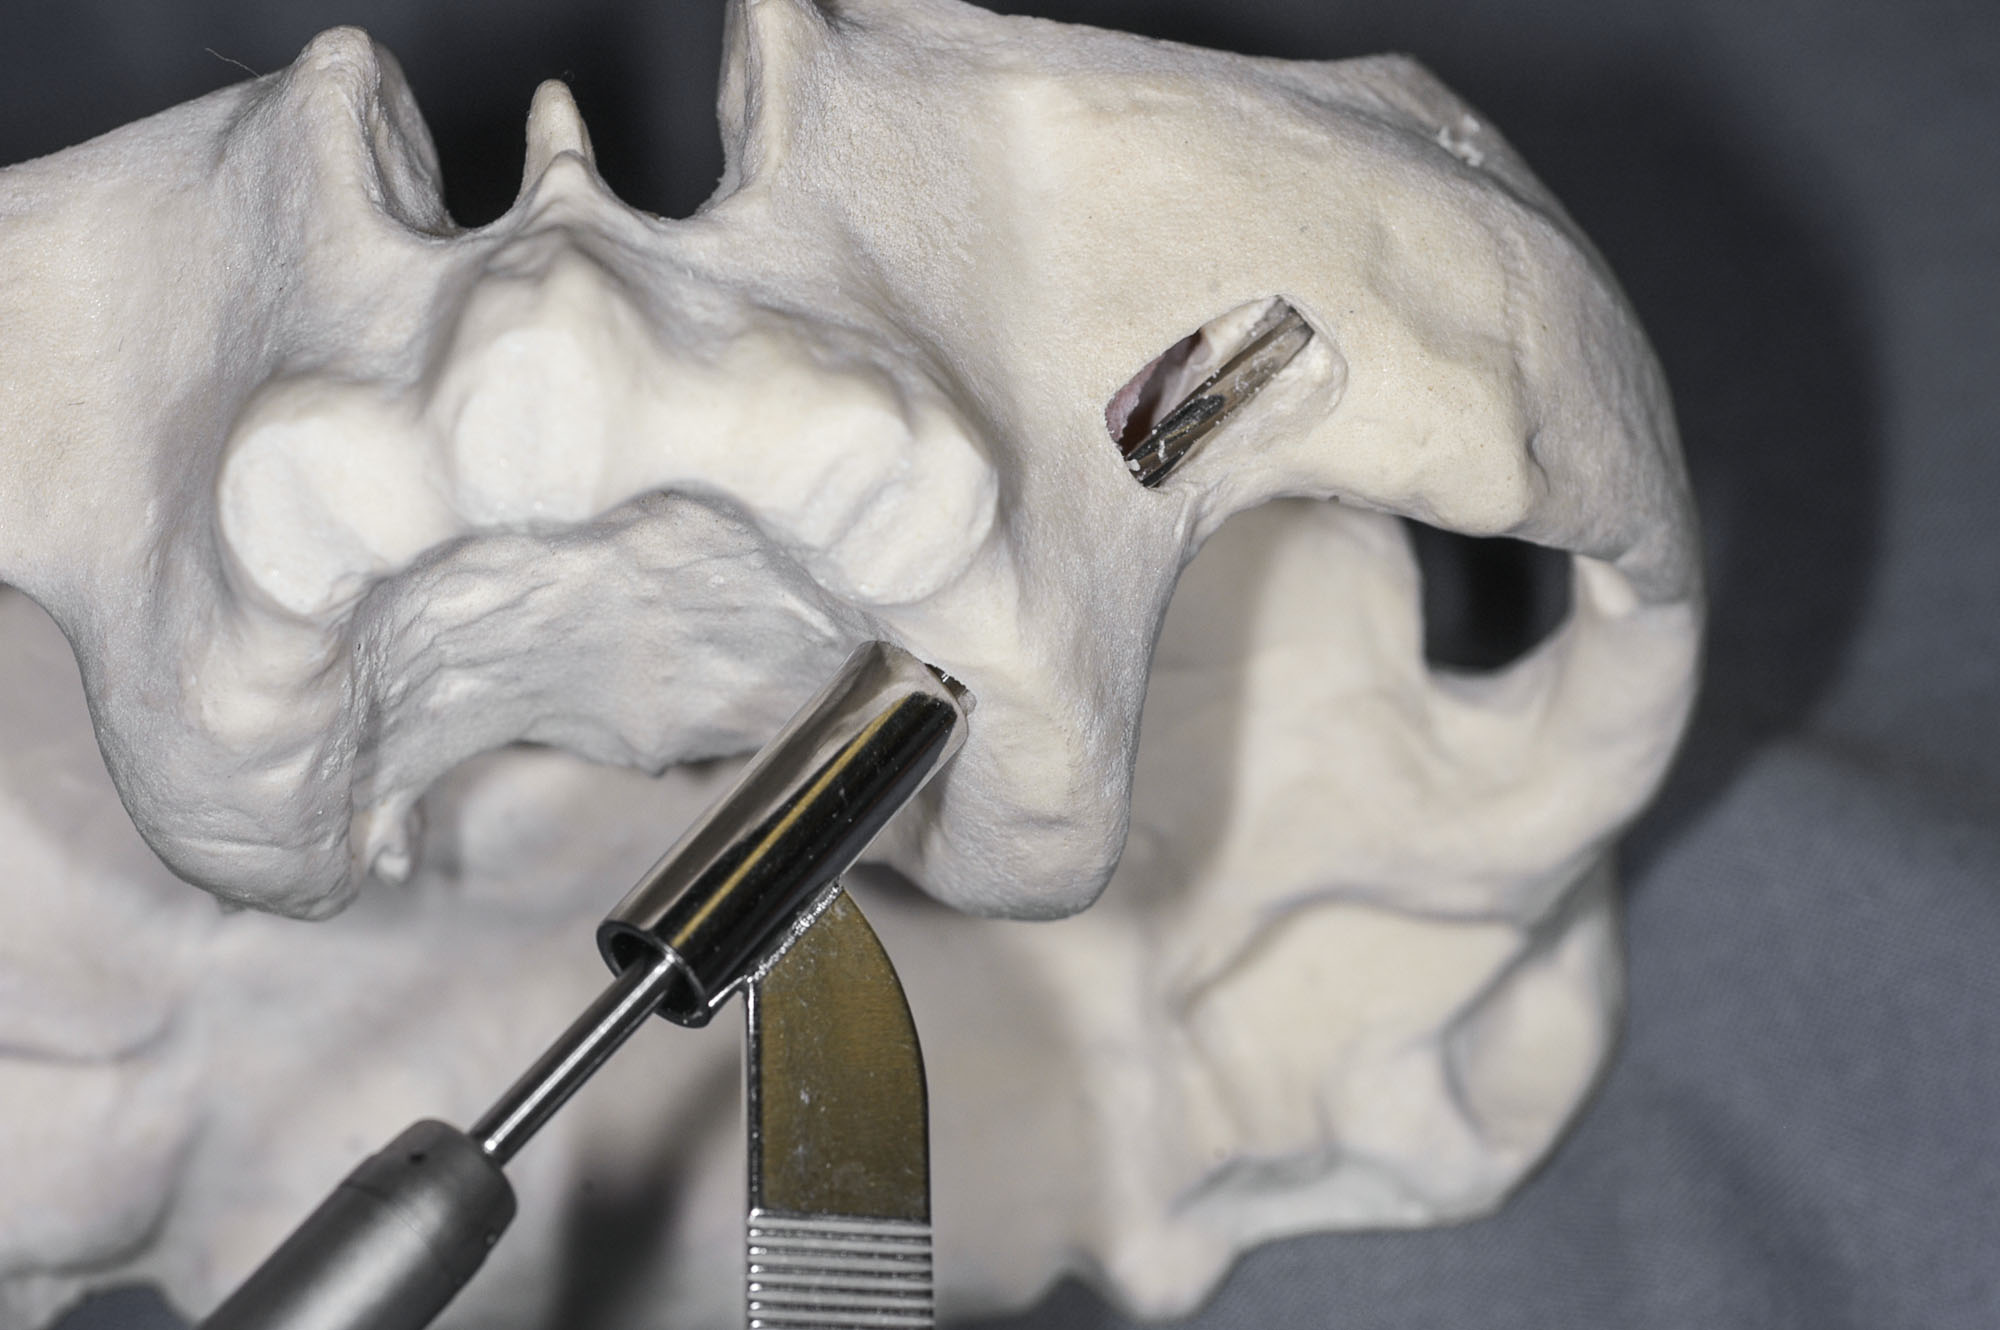

Na podstawie skanów CBCT można wydrukować modele kostne pacjenta w skali 1:1 w technologii FFF lub STL, co wydaje się szczególnie przydatne przy planowaniu zabiegu implantacji u pacjentów z ubytkami po resekcjach szczęk.

Wirtualne planowanie zabiegu w aplikacji NobelClinician na podstawie danych z CBCT.